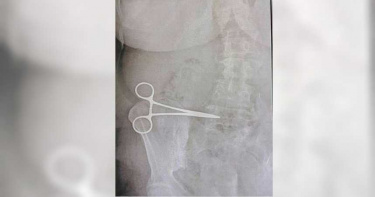

手術後持續腹痛 母親拍X光後驚見「腹中有剪刀」

土耳其一名母親想要改善腹部因為生產產生出來的皺紋問題,所以前往當地一家私人診所進行手術。但出院返家後,該名婦人的腹部一直莫名疼痛,直至兩個月後,婦人更換醫院進行檢查,沒想到當時幫她動手術的醫院,竟然遺留了一把手術用剪刀在他的腹部。根據《鏡報》報導指出,土耳其61歲婦人歐格蔓(Nurcihan Ogmen)因為生有七子,腹部有因為生產產生嚴重的皺紋問題,所以在3月時決定前往一家私人診所進行皮膚切除。當天手術在進行5小時候完成,歐格蔓就在隔日順利地出院。但返家後的歐格蔓一直感覺到腹部異常疼痛,曾經回到醫院回診,但醫生表示一切正常,為了這莫名的腹痛,歐格蔓幾乎每周都回去醫院看診,但一直都沒有獲得很好的改善。在腹痛兩個月後,歐格蔓決定前往其他醫院接受檢查,沒想到該間醫院的醫師幫歐格蔓進行X光拍照後,發現歐格蔓的腹中有一把手術用的剪刀,推測應該是上次幫他做皮膚切除時,醫師遺留在歐格蔓腹中所導致。最後歐格蔓接受緊急手術,將這把讓他腹痛難耐的剪刀給取了出來。事後,歐格蔓對先前執刀的醫師、醫院管理部門以及手術相關醫護人員提出告訴,目前幫歐格蔓進行皮膚切除手術的醫院並沒有任何回應。